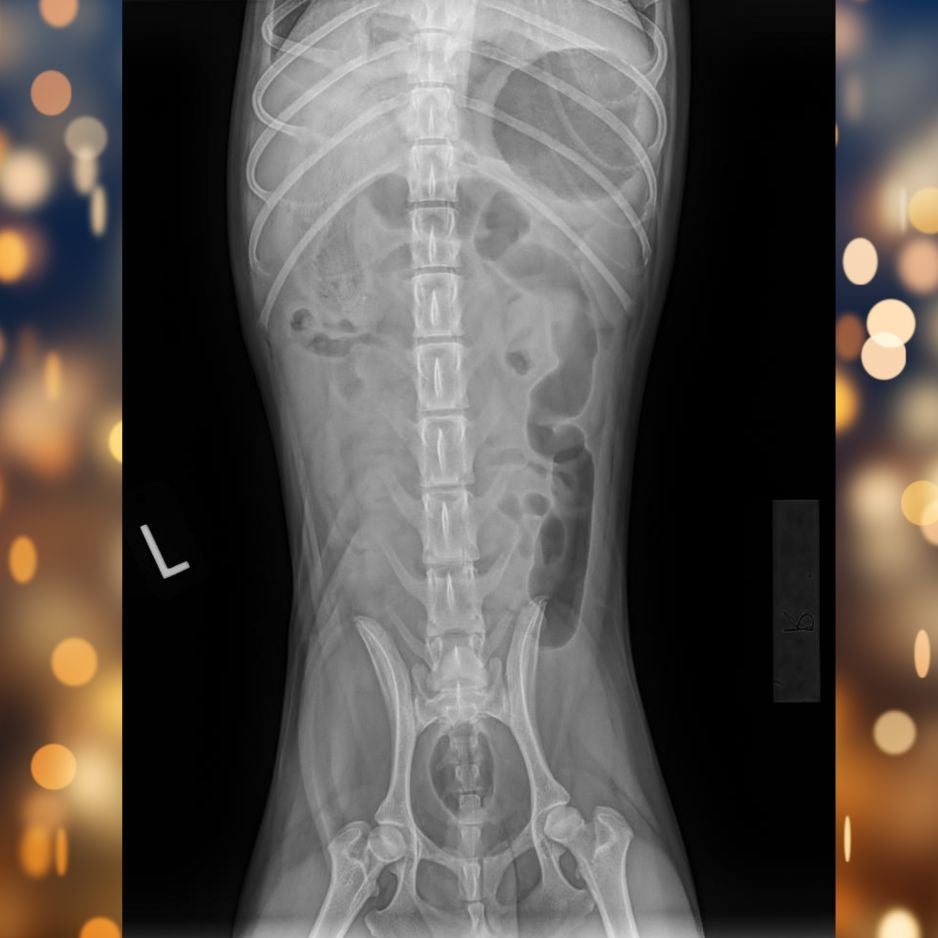

X-rays confirmed our suspicion — fabric material was visible in Tito’s small intestine, causing a blockage in his gastrointestinal tract. This meant food and fluids couldn’t move through normally, leading to pain, dehydration, and vomiting.

Tito X-rays